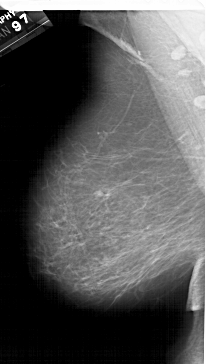

A_1615_1.LEFT_MLO

LEFT_MLO LINES 6541 PIXELS_PER_LINE 3706 BITS_PER_PIXEL 12 RESOLUTION 43.5 NON_OVERLAY